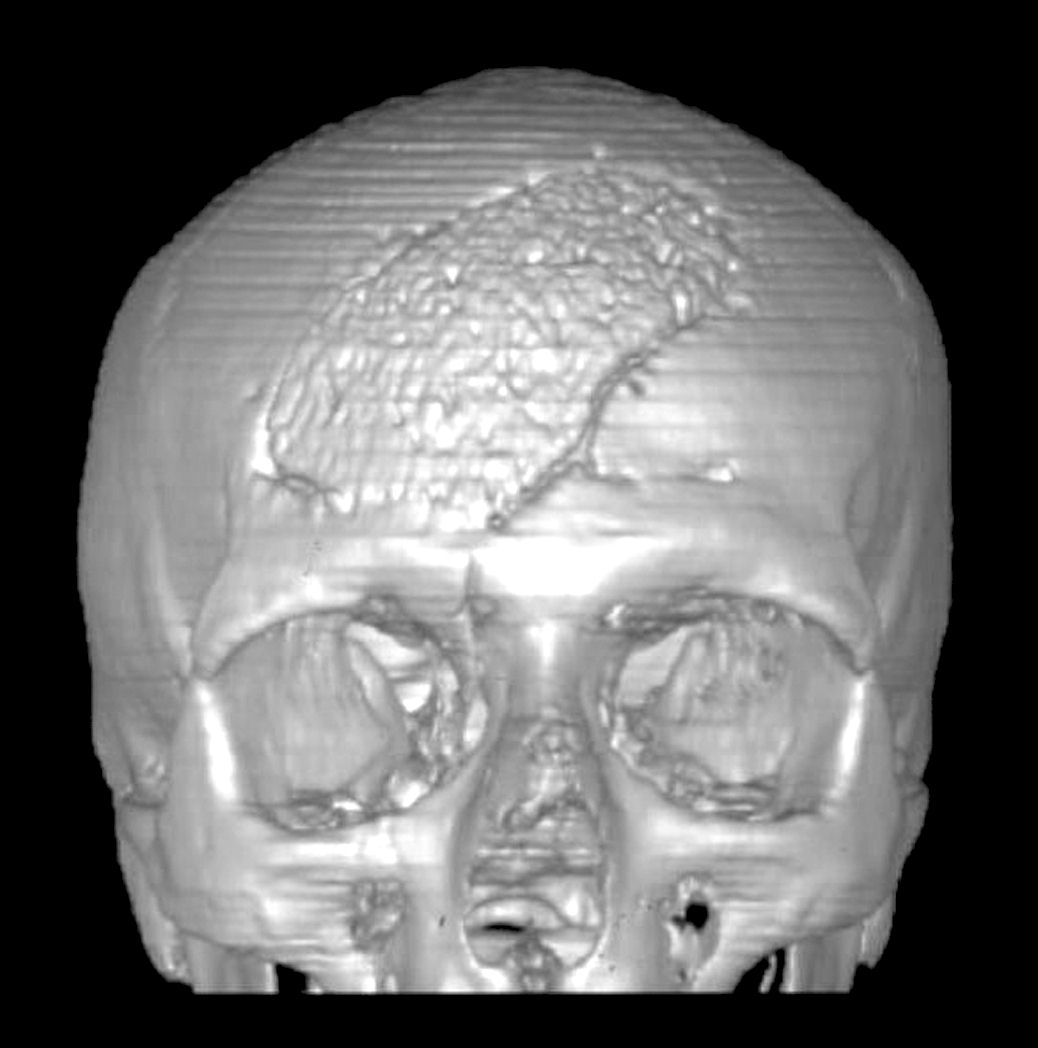

Si stanno conducendo studi mediante procedura di medicina nucleare per cercare di dimostrare in vivo, senza bisogno di prelievi bioptici, la progressione osteoblastica ed osteoclastica dalla periferia protesica verso il centro della stessa (Figura 3).

Figura

3. Indagine scintigrafica eseguita con tecnica trifasica e

SPECT a livello della teca cranica. Nelle immagini tardive in

regione frontale destra (a sinistra nelle immagini), in

corrispondenza della protesi cranica, si rilevano significative

tracce di captazione del radiofarmaco, con ipercaptazione

periprotesica. Evidenza alle indagine TC 3D (immagine a sinistra)

dell'estensione della cranioplastica in idrossiapatite porosa

frontale destra. |